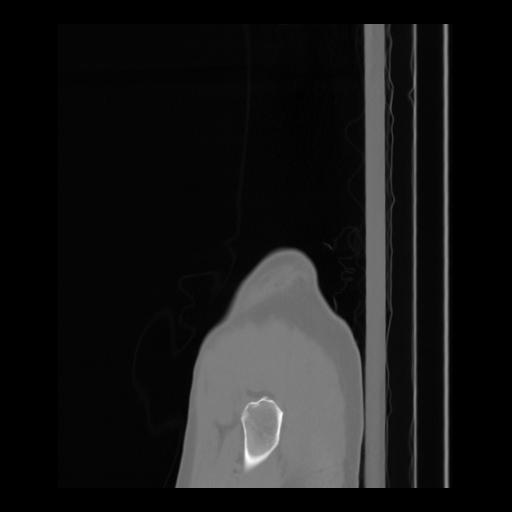

36 CUERPO,CE,Sagittal,3.000,CUERPO,Sagittal,